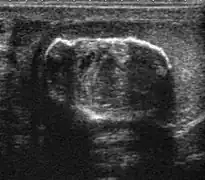

Primary leukemia of the testis is rare. However, due to the presence of blood-testis barrier, chemotherapeutic agents are unable to reach the testis, hence in boys with acute lymphoblastic leukemia, testicular involvement is reported in 5% to 10% of patients, with the majority found during clinical remission. The sonographic appearance of leukemia of the testis can be quite varied, as the tumors may be unilateral or bilateral, diffuse or focal, hypoechoic or hyperechoic. These findings are usually indistinguishable from that of the lymphoma [Fig. 9].

Fig. 9. Leukemia. Diffuse hypoechoic infiltrative lesions are seen involving the whole testis, indistinguishable from that of the lymphoma.